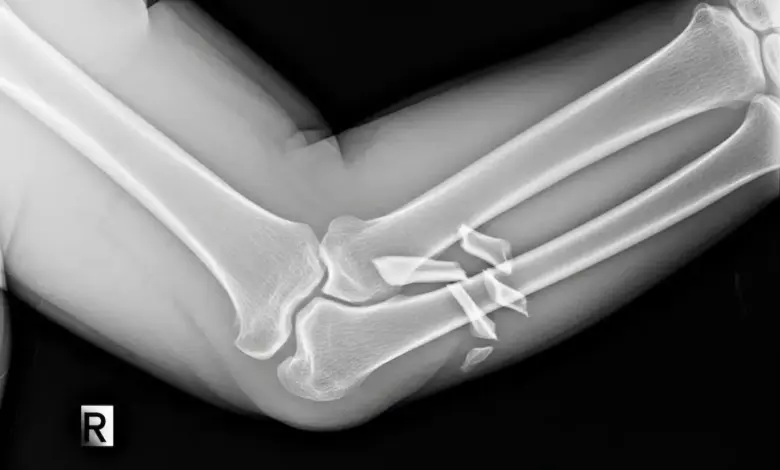

Na prática, o exame que costuma esclarecer o diagnóstico é o raio X, pois permite enxergar a linha da fratura, o posicionamento dos fragmentos e o quanto eles saíram do lugar.

Quando a quebra é mais complexa, o ortopedista pode pedir uma tomografia para enxergar melhor os detalhes da lesão e organizar o planejamento da cirurgia.